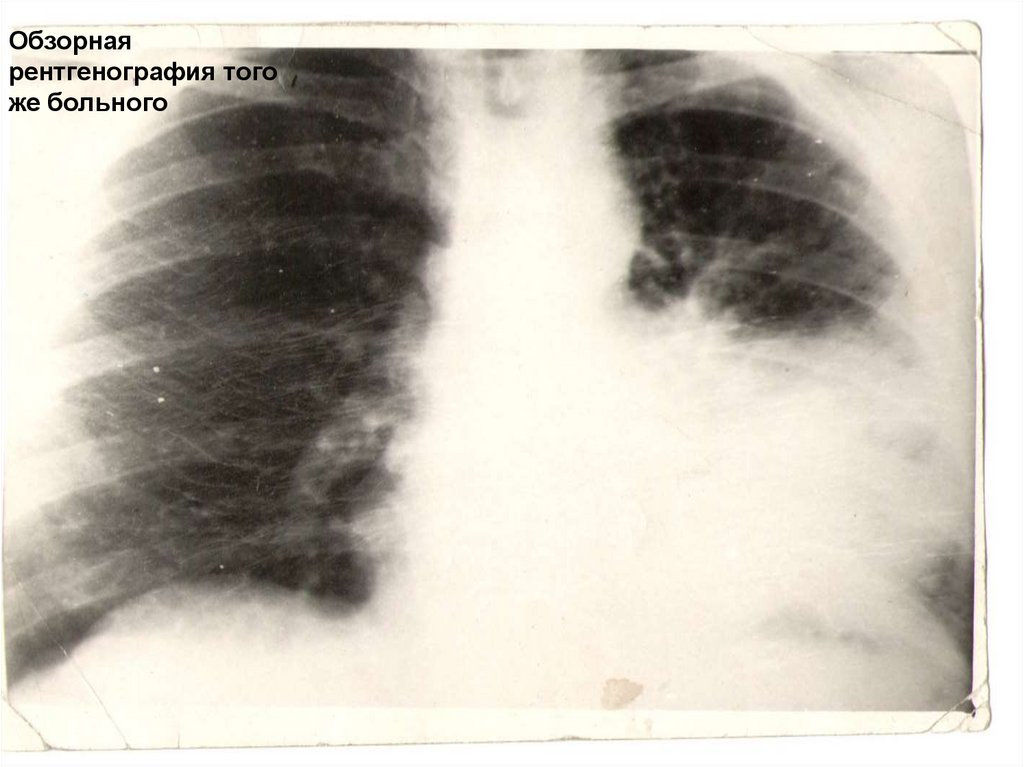

Обзорная

рентгенография того

же больного